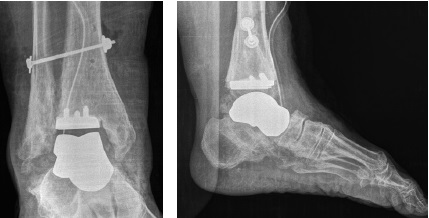

Then, according to the preoperative plan, the tibial component of the ankle endoprosthesis was implanted. The dimensions of the tibial component and the liner were calculated in advance and corresponded to intraoperative measurements. After implanting the tibial component and the polyethylene liner, a ceramic individual endoprosthesis of the talus \ was implanted without technical difficulties. After the implant was implanted, correction of deformation, tension of the ligaments, restoration of almost full range of movements in the ankle joint were noted (Fig. 6). The main stage of surgery was completed, the wound was sutured in layers. Drainage of the wound with active drainage for one day, aseptic dressing was applied, temporary immobilization with a deep back plaster splint.

Fig. 6. Intraoperative X-rays of the ankle joint in the AP and lateral planes: the presence of a talus implant, a tibial component of the ankle joint endoprosthesis, syndesmotic screw is visualized; restoration of the ankle joint and foot contours

The edema maintained of the operated lower limb for 3 months after surgery, significantly decreasing overnight. The control radiography showed no signs of instability, maintaining a good anatomical position of the talus implant and the tibial component of the ankle endoprosthesis. The total volume of passive and active movements in the ankle joint at the time of the last control examination is 28°, of which the back flexion is 12° plantar flexion is 16°, which can be characterized as an acceptable result compared to the normal range of motion in the joint (Fig. 7, 8).

Fig. 7. Control X-rays of the ankle joint 20 months after surgery: a — AP plane, good position of hardware is noted, preservation of the ankle contours; b, c — functional X-rays in the lateral plane of the plantar and dorsal flexion: good position of the endoprosthesis components is noted, total ROM is 28°